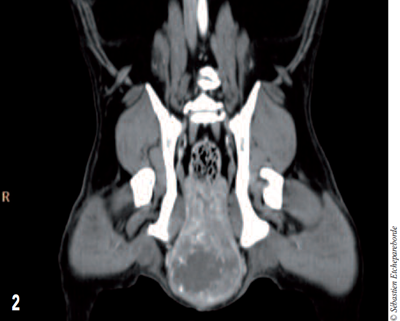

photo 2

Photo 2 – Coupe longitudinale de la masse envahissant le bassin.

Une sonde urinaire avait été mise en place préalablement pour repérer l’urètre au scanner. La masse mesurait 10 cm de long sur un diamètre d’environ 5 cm. Aucune des structures environnantes ne semblaient envahies par la masse.